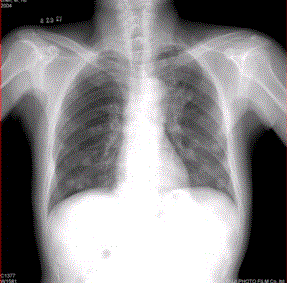

问题 患者男,45岁,因肝硬化、肝癌行肝移植术后6个月,咳嗽2周,来院复查。CR及CT影像如下图。 对于该病例,首选诊断为

选项 A.肺结核 B.肺转移瘤 C.肉芽肿性疾病 D.支气管肺泡癌 E.淋巴瘤 F.支气管肺癌

答案 B